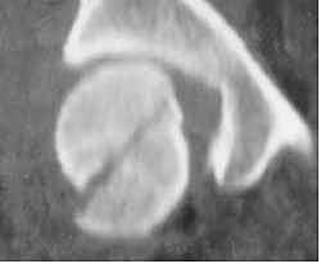

Luxatie

gleno-humerala

gleno-humerala Luxatie gleno-humerala

Aspect CT Aspect

CT